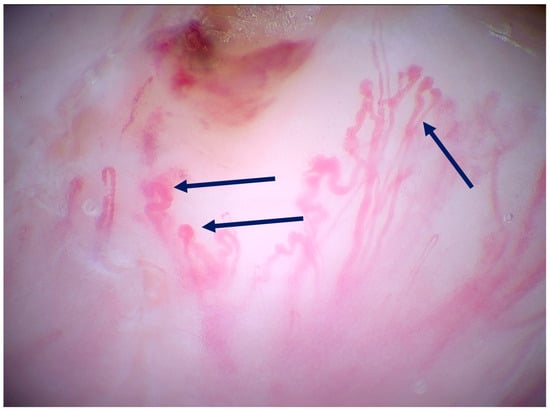

| Pogorzelska-Dyrbuś et al. (2025) [24] | Case series | A 73-year-old female patient with a solar lentigo on her left cheek, and a 55-year-old female patient with lplk on her right arm. | Solar lentigo: Brown-reddish uniform polygonal structures corresponding to keratinocytes that contoured follicular openings, areas of dense arrangement of brown polygonal structures with well-defined borders. Lichen planus-like keratosis: Numerous blue-purple large structures corresponding to melanophages with straight linear vessels. | V |